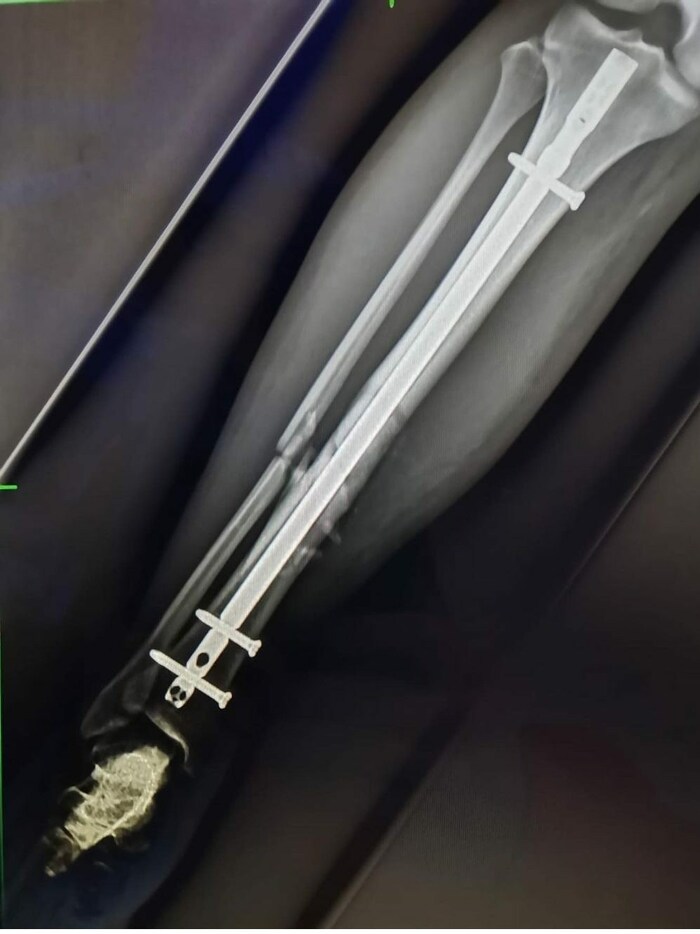

Bei dem Eingriff in den USA wurde Nußbaumer ein Marknagel eingesetzt.

Bei dem Eingriff in den USA wurde Nußbaumer ein Marknagel eingesetzt.(Bild: zVg)